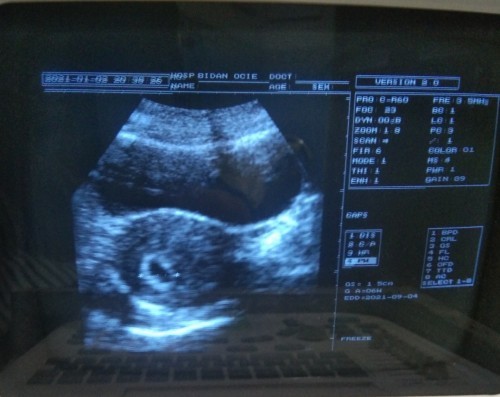

usia 7 w